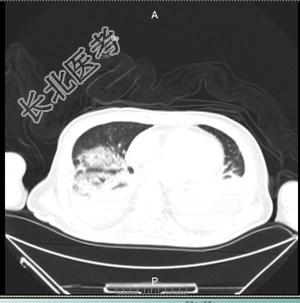

辅助检查:FIO250% PH7.333 PaCO255.6mmHg PaO239.9mmHg cLac2.7mmol/L血常规:WBC19.16×109/L,N%87.8%,血红蛋白:108g/LCRP:184.3mg/L血沉:40mm/hPCT:8.34ng/ml支气管镜下:支气管黏膜充血、水肿,可见少许食物残渣、大量白色粘痰。吸痰后各支气管腔均通畅。胸部CT:两肺多发渗出。痰培养:大肠埃希氏菌血培养:阴性支气管镜:镜下发现拉丝样白色粘痰